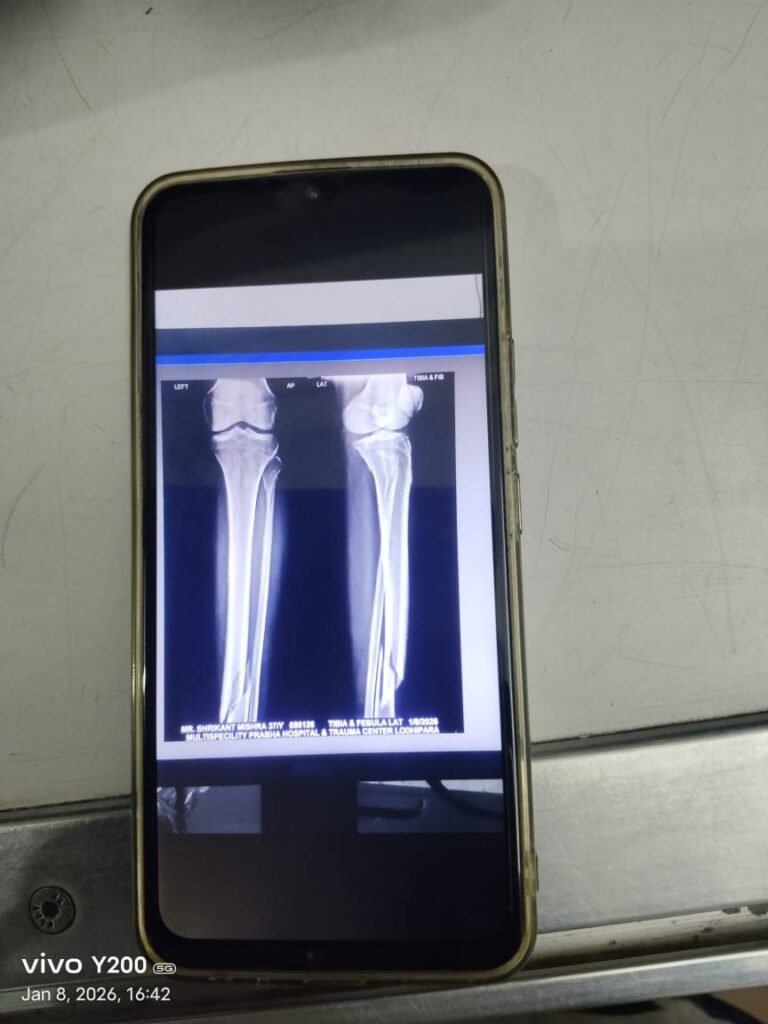

घटना के बाद पेट्रोलिंग पार्टी द्वारा घायल आरक्षक को तत्काल निजी अस्पताल प्रभा हॉस्पिटल, सरकंडा में भर्ती कराया गया। चिकित्सकों के अनुसार आरक्षक के बाएं पैर की हड्डी टूट गई है, जिससे वे चलने-फिरने में असमर्थ हैं। साथ ही उनके मुंह में भी गंभीर चोट आई है।